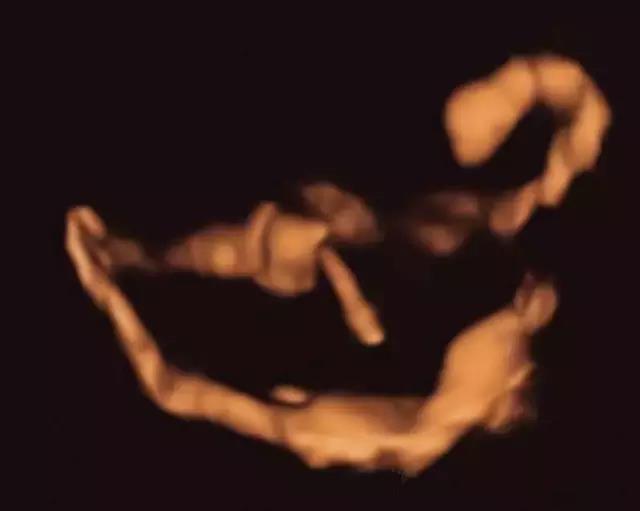

四维子宫输卵管超声造影是指向宫腔注入超声造影剂后,实时三维立体显示造影剂在宫腔、输卵管和盆腔内流动、分布的的显影过程,来评价输卵管通畅度及诊断部分的宫腔病变。随着声学造影剂和超声仪器设备的发展,子宫输卵管造影技术日趋成熟,逐渐成为临床评估输卵管通常度的首选筛查及诊断方法。

子宫输卵管超声造影实时动态图

双侧输卵管通畅